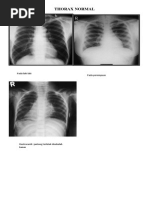

Foto toraks yang baik

Mencakup seluruh rongga dada: Dari iga pertama sampai ke sinus kostofrenikus. Tidak terjadi rotasi tubuh anak: Iga anterior kanan dan kiri sama panjang dan simetris. Keadaan ini akan mempengaruhi gambaran mediastinum dan besar jantung Lordosis: Bila terjadi lordosis arah ujung iga anterior akan mendatar atau mengarah ke kranial. Keadaan ini akan mempengaruhi lebar mediastinum superior dan besar jantung serta memberikan bentuk iga yang tidak normal

Foto toraks Lateral

Iga posterior berimpitan Tulang belakang tidak rotasi Seluruh toraks harus masuk dari apeks sampai diafragma

Kondisi foto toraks yang baik Corakan vaskular paru

sentral 2/3 lapangan paru, tidak kabur Trakea dan bronkus besar terlihat pada foto Gambaran tulang belakang terlihat melalui jantung